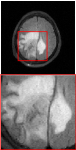

Figure 5 provides the qualitative comparison of the various methods on the four datasets at a scale of 4. The top, second, third, and bottom rows are the SR results under the FastMRI, clinical brain, clinical tumor and clinical pelvic datasets, respectively. The red boxes indicate the zoom-in region of complicated anatomical structures along with their corresponding error maps. Note that the brighter textures in the error maps, the lower the quality of the reconstructed images. As can be seen, compared to methods based on Transformers and CNNs, diffusion-based methods like DisC-Diff and DiffMSR (Ours) are capable of reconstructing high-realistic images with promising reconstruction metric scores (PSNR and SSIM). Nevertheless, while DisC-Diff can reconstruct high-precision MR images, it does not preserve the structure present in the original HR images, introducing some additional information that can affect medical diagnosis. In contrast, our method combines DM and PLWformer, which can preserve the original image’s structure while restoring high-frequency information.

In this section, we present more visual qualitative comparisons. Figures 8, 9, 10, and 11 show the reconstruction results of each method in FastMRI, clinical brain, clinical tumor, and clinical pelvic, respectively. As can be seen, although DisC-Diff can reconstruct MR images with high-frequency information, it fails to preserve the structure and content of the original Target HR image effectively, resulting in image distortion. In contrast, our proposed DiffMSR can restore high-frequency information while preserving the structure of the original HR image, indicating the effectiveness of the joint use of DM and PLWformer.